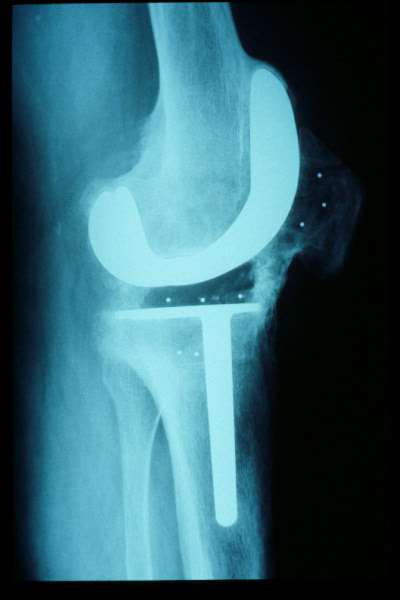

Prótesis completa de rodilla. Situación postquirúrgica.

Prótesis completa de rodilla. Situación postquirúrgica. Lateral.

Prótesis completa de rodilla.Lateral.

Prótesis completa de rodilla. Frontal.